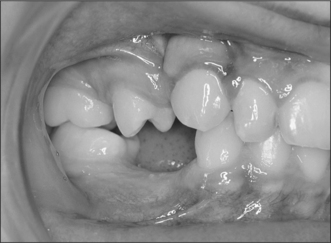

Although simple exposure is satisfactory for superficially placed teeth situated close to the surface and impacted in soft tissue alone, most unerupted teeth are located more than 3–4 mm from the oral mucosal surface and the crown cannot be seen completely after raising a flap (Fig. 12.3). As impaction of unerupted teeth usually involves hard tissue as well as soft tissue, all bone covering the tip of the crown as far as the maximum width of the tooth should be carefully removed. If the tooth is superficial and covered by thin bone this can often be undertaken using a scalpel blade. Where bone coverage of the unerupted tooth is more extensive, a small rose head bur or hand-held chisel may be used to clear overlying bone from the crown. Extreme caution must be taken to avoid damaging the tooth crown and the roots of the adjacent teeth. Unnecessary removal of bone should also be avoided. Whilst soft- and hard-tissue exposure of unerupted teeth is in some instances successful, most commonly (and especially in the case of deeply impacted teeth) the created surgical defect will become re-epithelialized if patency is not maintained. The defect is, therefore, packed with an antiseptic gauze dressing or a glass-ionomer cement bonded to the tooth crown in order to inhibit contraction and re-epithelialization (Fig. 12.4). Postoperative antibiotics are seldom indicated unless there is a known increased risk of wound infection, e.g. patients with insulin-dependent diabetes mellitus.

Fig. 12.3 Raising a palatal flap reveals a totally embedded canine that will require bone removal to expose it.